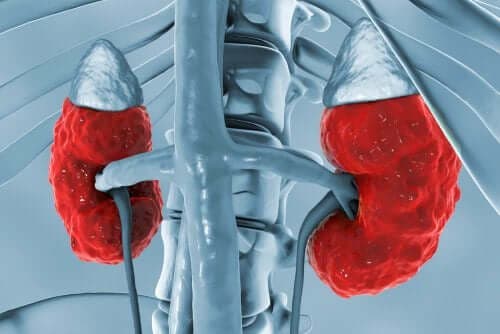

På nyrerne

Dets handling på nyrerne indebærer en række processer, som koncentrerer urinen. Ved at fremme denne koncentration, producerer vasopressin genoptagelsen af frit vand til den ekstracellulære væske.

Vasopressin handler på nyrerne ved at forårsage tre primære effekter:

- Det øger permeabiliteten i indledende og kortikale samlerør. Derudover øger det permeabiliteten i den ydre og indre medullære kanal i nyrerne. Således genoptages vandet og der er en udskillelse af mere koncentreret urin.

- Det øger også permeabiliteten af den indre medullære del af samlerøret til urinsyren.

- Som det sidste, er der en øget optagelse af natrium gennem den stigende del af Henle´s loop.